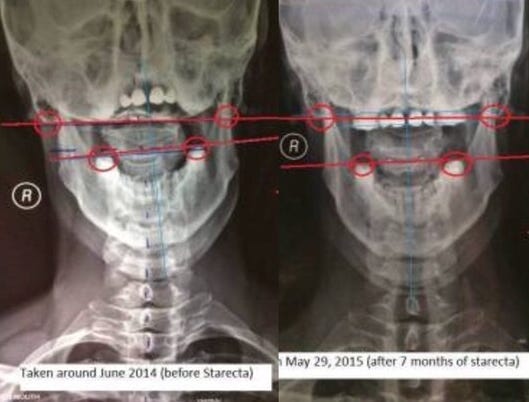

先來看看一張 X 光片:那是我在 2015 年拍攝的頭顱 X 光。當顱骨「洩氣」時,它會扭曲變形。上面提到的這張 2015 年的 X 光影像是我的頭顱,它曾在網路上流傳,被翻譯成俄文、中文甚至其他語言出現在許多網站上。2015 年時,我才剛開始學習運用這套生物力學理論,那時我的理解還遠遠不夠完整。

2015 年初,我使用了一種稱為「Starecta」的 DIY 齒顎生物力學技術,這是由幾位義大利人創立的方法。主要的創始人是一個叫做 Moreno 的人。我記得當時我還與他有一些交流,因為在義大利境外,我大概是第二個嘗試 Starecta 的人。總之,我親眼看到,透過調整口腔內的生物力學,可以讓扭曲的身體慢慢恢復正常。然而,後來當我一度搞砸了步驟時,也看到身體再次扭曲回去。我看到的這些現象並不只是我「以為」的主觀感受……而是在 X 光片上清清楚楚地顯示出來的。看看那張 X 光對比圖,右邊的顱骨相較於左邊,明顯沒有那麼「扭曲」了吧?